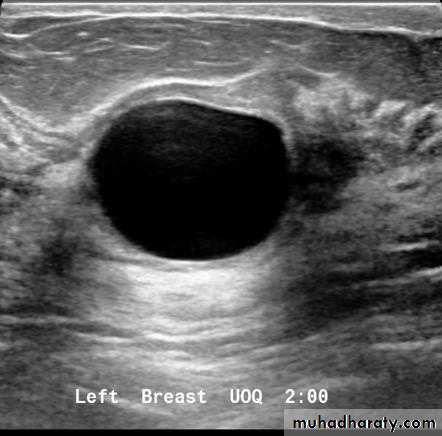

Cysts can be simple fluid-filled sacs (known as simple cysts) or can be partially solid (known as complex cystic and solid masses). Simple cysts are benign (not cancer) and don’t need to be biopsied. If a mass is not a simple cyst, it is of more concern and might need to be biopsied to be sure it isn’t cancer